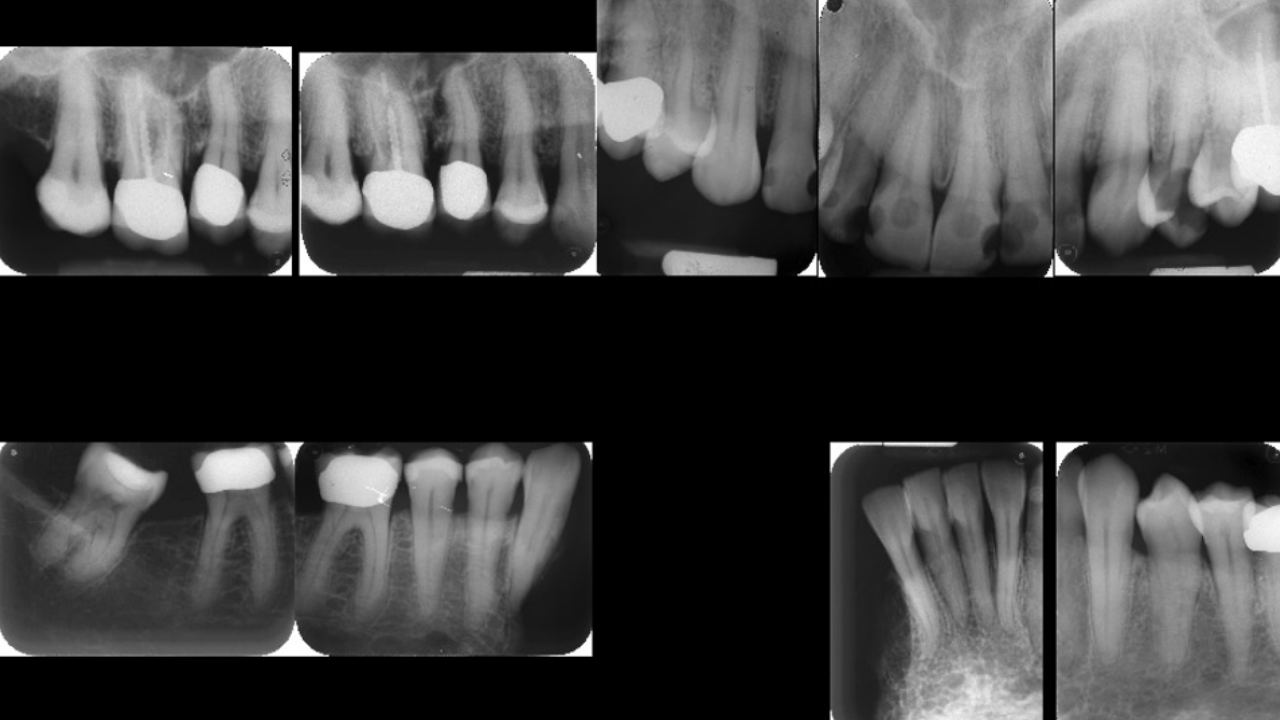

หลังจากตรวจเช็กฟันจากภายนอกแล้ว ขั้นตอนต่อไปเป็นการเอกซเรย์ฟันทั้งปาก โดยใช้ฟิล์มเล็กๆ กับฟันทุกซี่ แล้วนำข้อมูลที่ดูด้วยตากับข้อมูลเอกซเรย์มาพิจารณาร่วมกัน ซึ่งการเอกซเรย์จะเห็นข้อมูลมากกว่า เช่น การอุดฟันที่ด้านข้าง การรักษารากฟัน หรือฟันคุด

การตรวจพิสูจน์จากฟันมีความน่าเชื่อถือเทียบเท่ากับการตรวจ DNA แต่มีค่าใช้จ่ายน้อยกว่า จึงนิยมมากในต่างประเทศ เนื่องจากต่างประเทศมีการเก็บข้อมูลฟันก่อนเสียชีวิตอย่างชัดเจน สามารถสืบค้นได้ง่าย ส่วนการเก็บตัวอย่าง DNA มีขั้นตอนการเก็บยากกว่า ต้องเก็บในอุณหภูมิต่ำและต้องระวังการปนเปื้อน ซึ่งการเชื่อมระบบเก็บข้อมูลทันตกรรม สิ่งสำคัญสำหรับการพิสูจน์อัตลักษณ์ของบุคคลด้วยนิติทันตวิทยา คือประวัติการรักษาฟันก่อนการเสียชีวิต